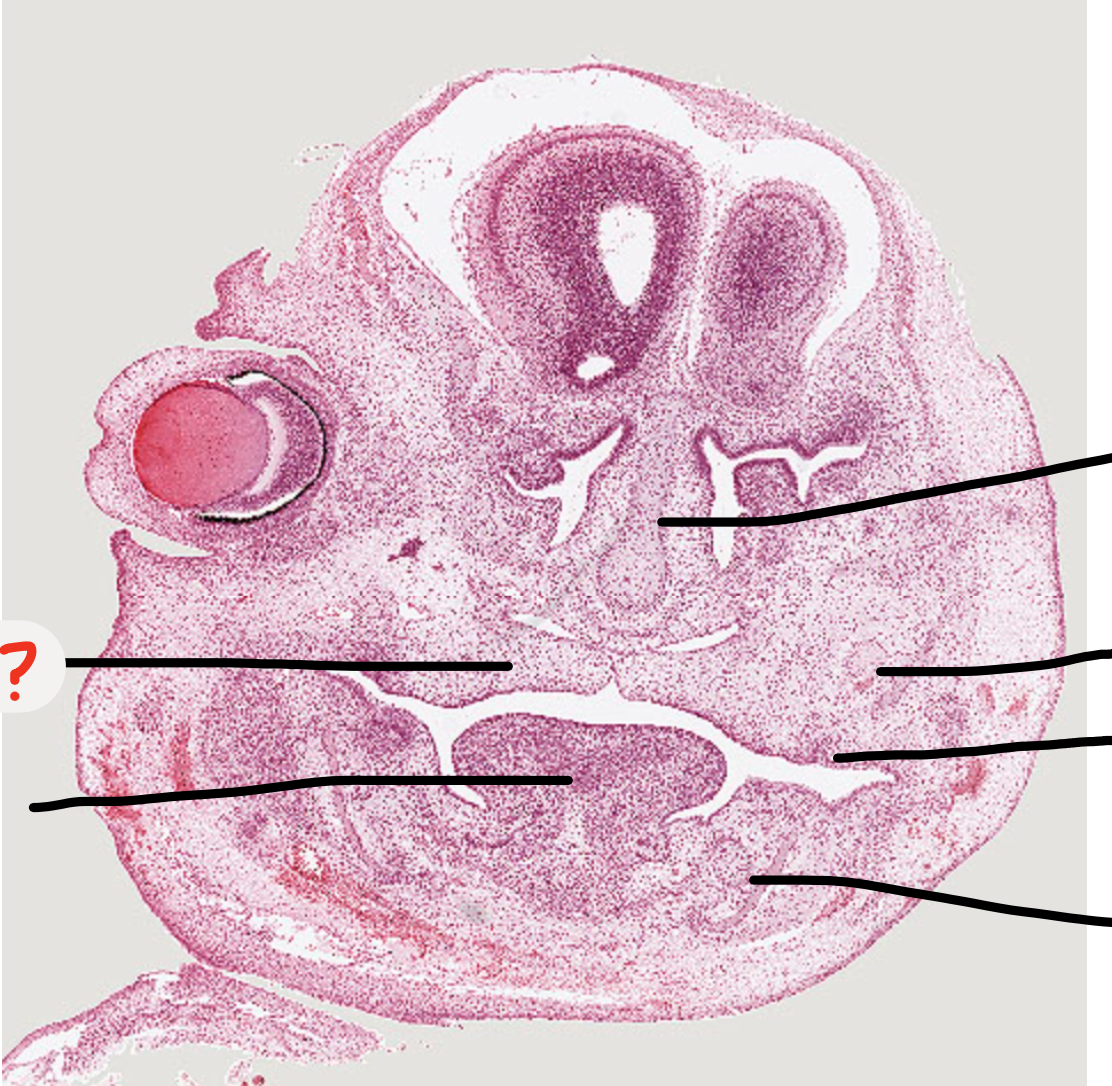

what process is this?

mandibular process

5

2

Q

A

maxillary process

How well did you know this?

predict what age the embryo is, why?

Week 7 as palatal shelves down lateral tongue and tongue takes up most of the space

Week 6 is when see the first evidence of tooth development